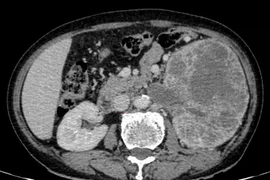

(Kiến Thức) - Bệnh viện Ung Bướu Hà Nội vừa phẫu thuật cắt bỏ khối u khổng lồ nặng gần 2kg cho một bệnh nhân ung thư thận. Đây được xem là trường hợp hiếm gặp với kích thước u quái to gấp 5 lần quả thận bình thường.